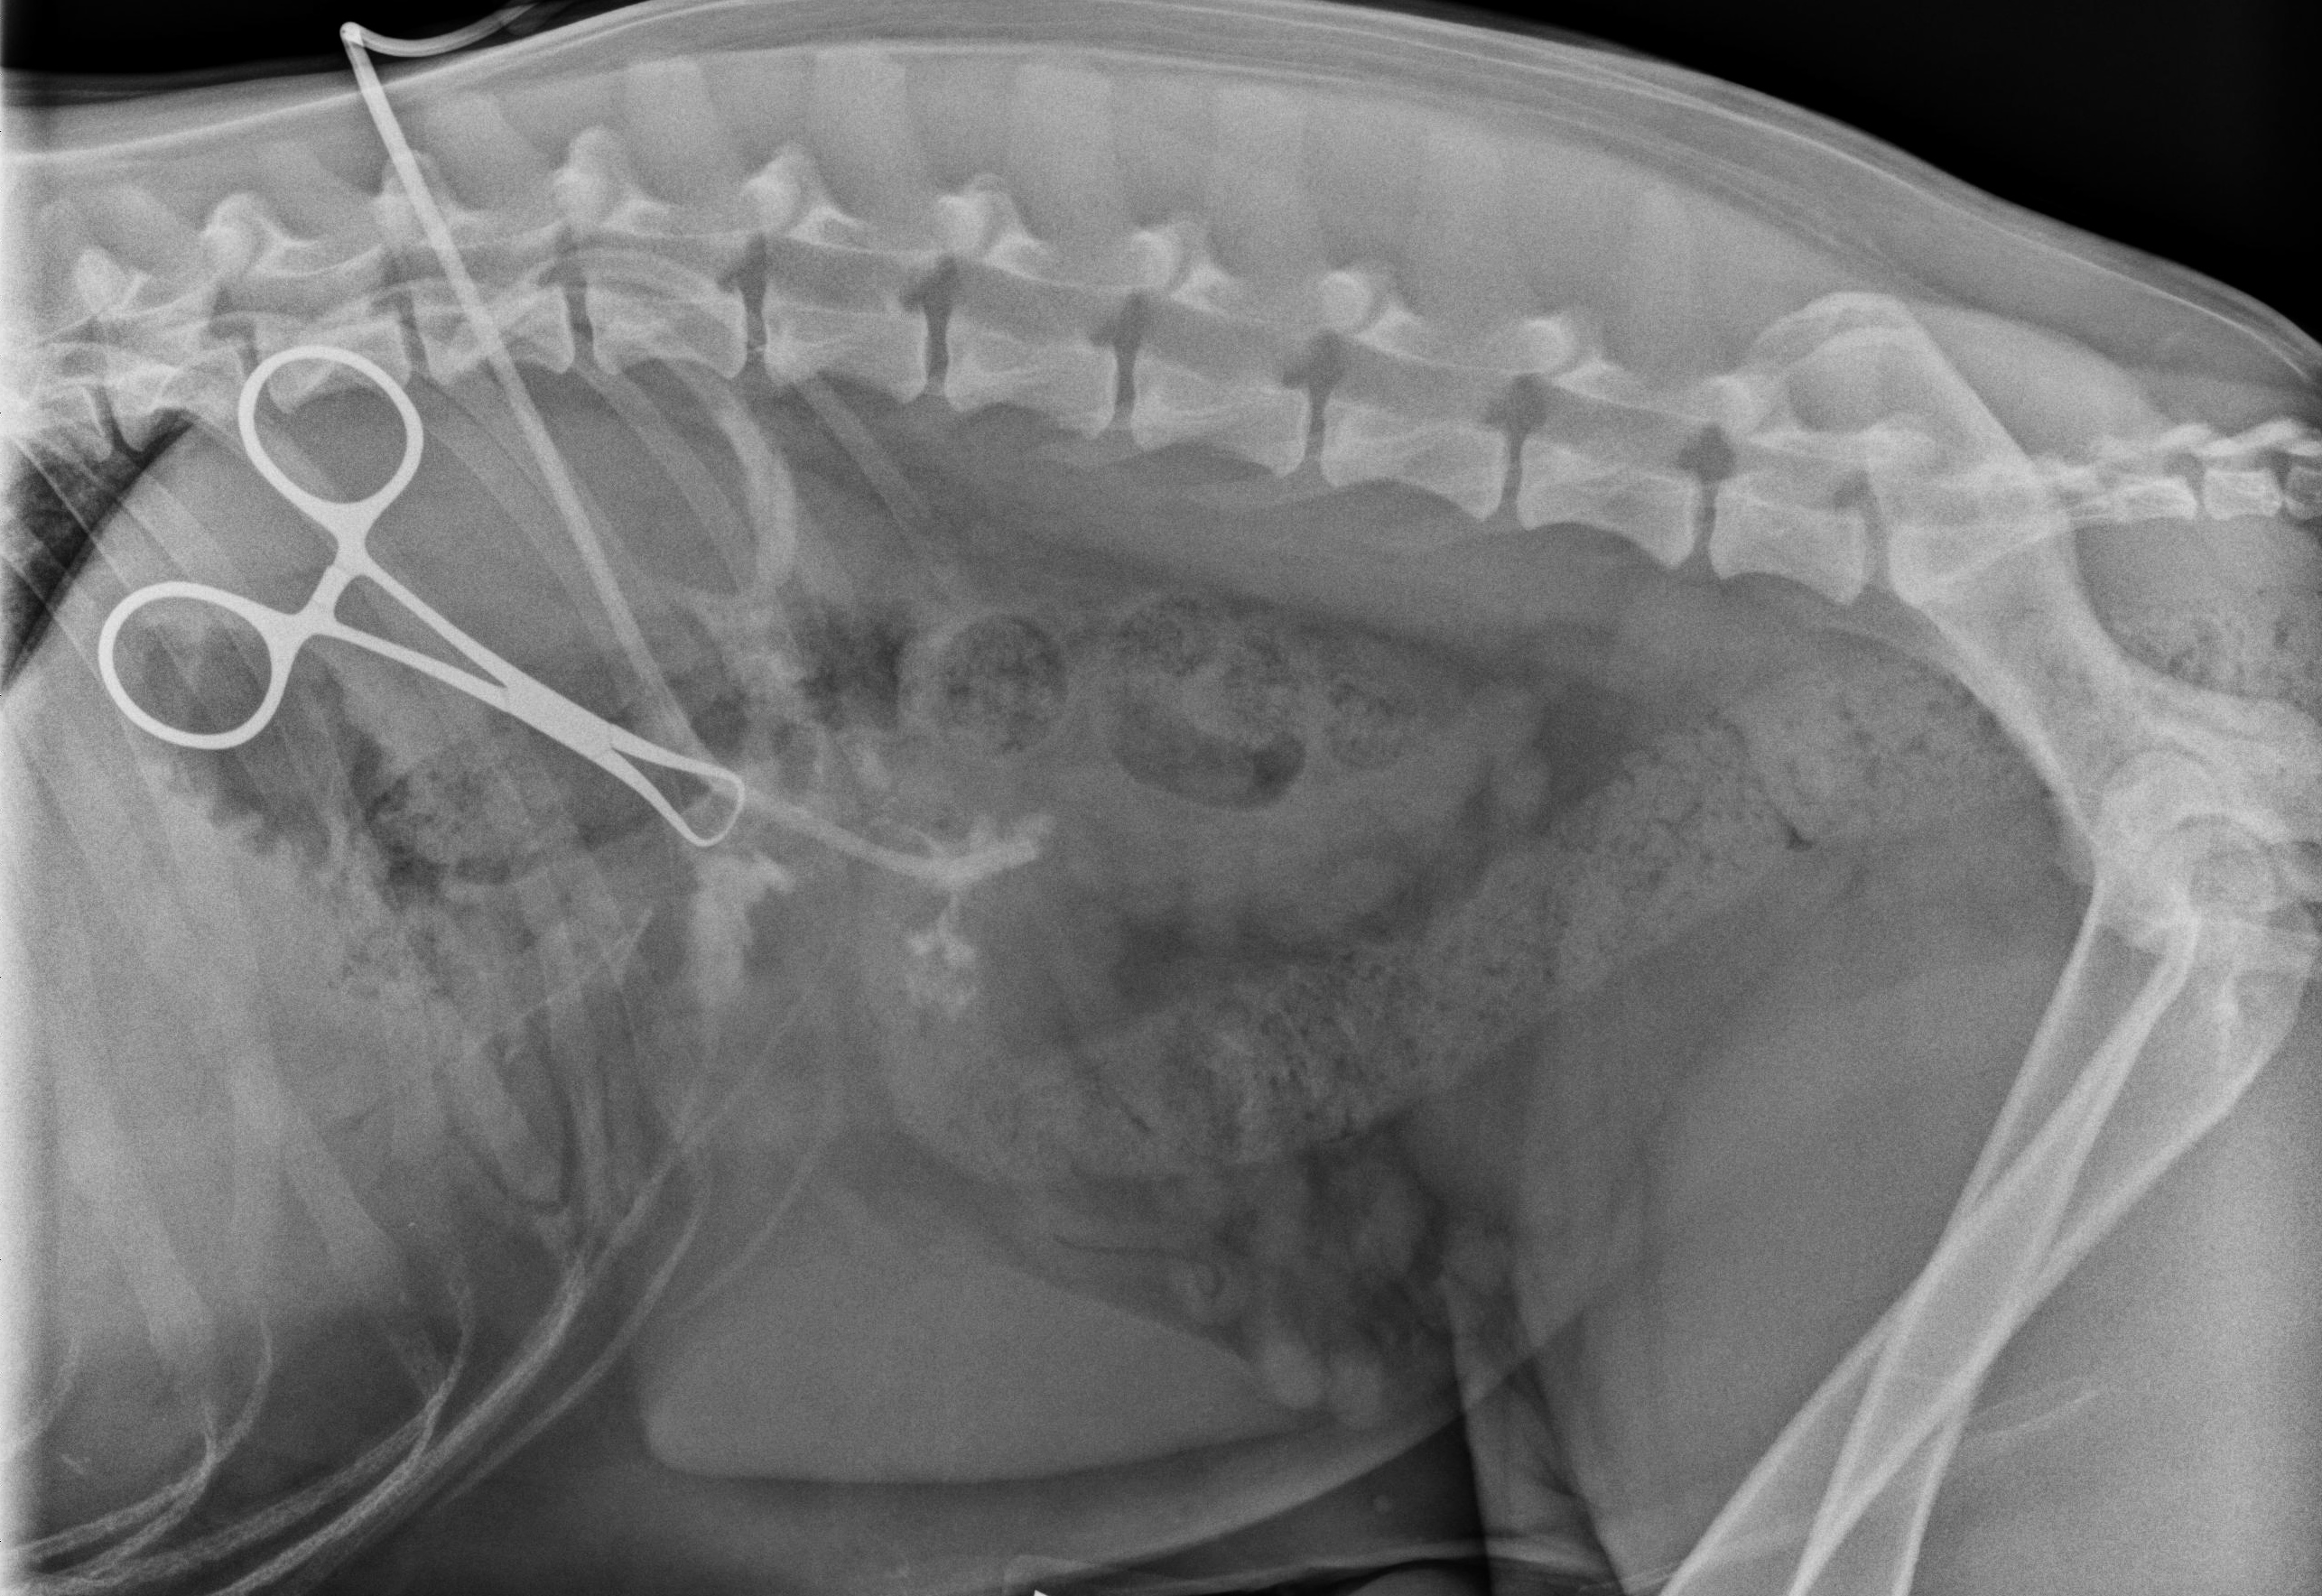

The next step for Luke was to perform some basic diagnostics including some radiographs (x-rays) of both his thorax (chest) and abdomen to rule out anything obvious or a communication from the outside into these body cavities. The x-rays were relatively unremarkable. With Luke under anesthesia just prior to surgery, a contrast study called a fistulogram was performed. A foley catheter was introduced into the non-healing wound and contrast fluid was injected. This fluid will show up white on x-rays. On this test, we were able to see some uptake of the contrast around an object in between the 11th and 12th rib. This test was very useful in showing us where we needed to focus our attention surgically.

The video pretty much says it all! On dissection in between the 11th and 12th rib (deep to the rib) we found a stick that was lodged there and it was successfully removed. This was a very gratifying surgery. You may be asking, were was the stick – which is an excellent question, did it come from the abdomen, chest, etc? If there was direct communication within the abdomen, then we would be concerned with a septic (infection) peritonitis and likewise if it were within the chest cavity we would be concerned with a pyothorax (infection in the chest cavity). To help us determine this, another foley catheter was introduced (after copious flushing) into the space that was occupied by the stick and everything else was closed around the catheter. Contrast was injected into the catheter and a x-ray taken which showed the contrast in the stomach and not in the body cavity. Sequential x-rays were taken which showed the contrast in the gastrointestinal tract and not outside.

Amazingly, I believe Luke had swallowed the stick at some point (longer than 6 months ago) and the stick had migrated from the stomach wall to the body wall. Most likely the stomach had been tacked or pinned to the body wall creating what is called a stoma, sealing the stomach to the body wall. Luke is quite a remarkable dog for withstanding this condition. On multiple rechecks since surgery, he has been doing very well – like nothing every happened. He is one for the record books!!!